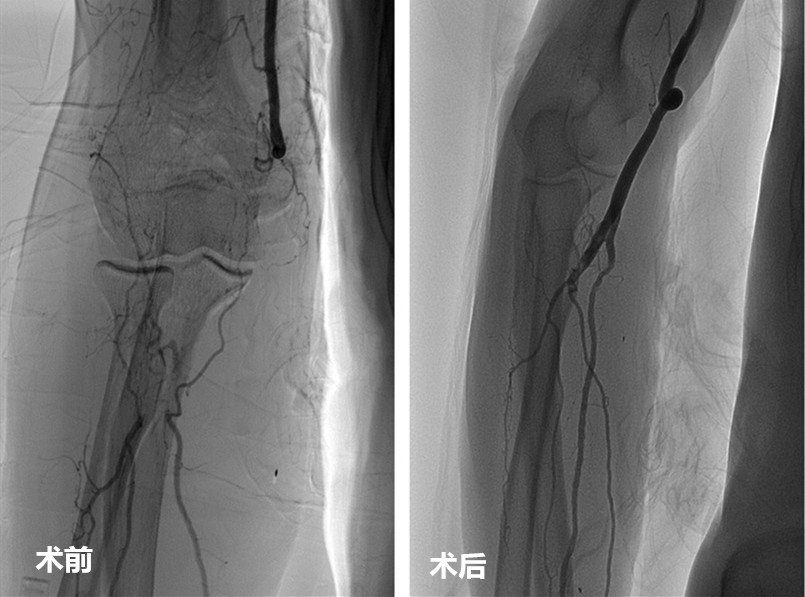

日前,今年76岁的吴大爷由我院介入团队行“DSA下右上肢动脉闭塞再通术”,微创置管溶栓,避免了传统手术“动刀”的风险。

引入DSA后,我院介入团队可独立开展介入取栓术等高难度术式。在DSA下,通过导管、导丝、支架等介入器材,团队可直接在血栓位置开通血管。相较传统治疗方式,介入治疗使用的溶栓药物剂量少,创伤小,出血风险低,更为精准高效,是广大患者的福音。